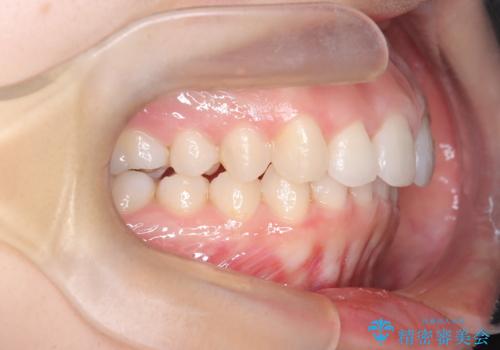

【インビザライン】前歯を引っ込めたい

- 前歯が出ていることを主訴に来院された患者様です。

抜歯を希望されなかっため、臼歯部の遠心移動やIPRを行い配列を行っています。

抜歯をしていない矯正となるため、口元に大きな変化は認められません。